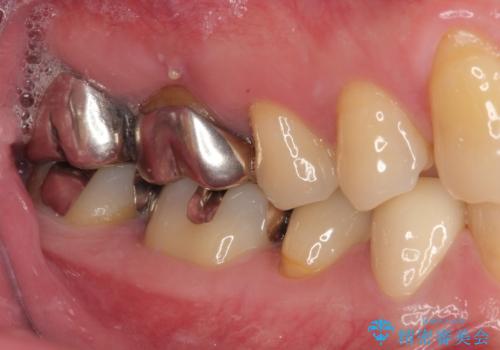

- 右下の銀歯が取れたとのことで来院された患者様です。以前にも取れていたところで、メタルインレーの不適合も認めていたため、次回外れたらオールセラミッククラウンにやり替えていくことを説明していたため、オールセラミッククラウンによる補綴治療を行っていくことにしました。

拡大鏡視野下で虫歯を除去しオールセラミッククラウンに適した形に整えました。

歯と歯茎の間に圧排糸と言われる糸を入れてシリコーン印象材にて型どりをしました。

審美面、機能面共に満足していただけました。

順次、後ろにある不適合のメタルインレーの部位をやり替えていく予定です。